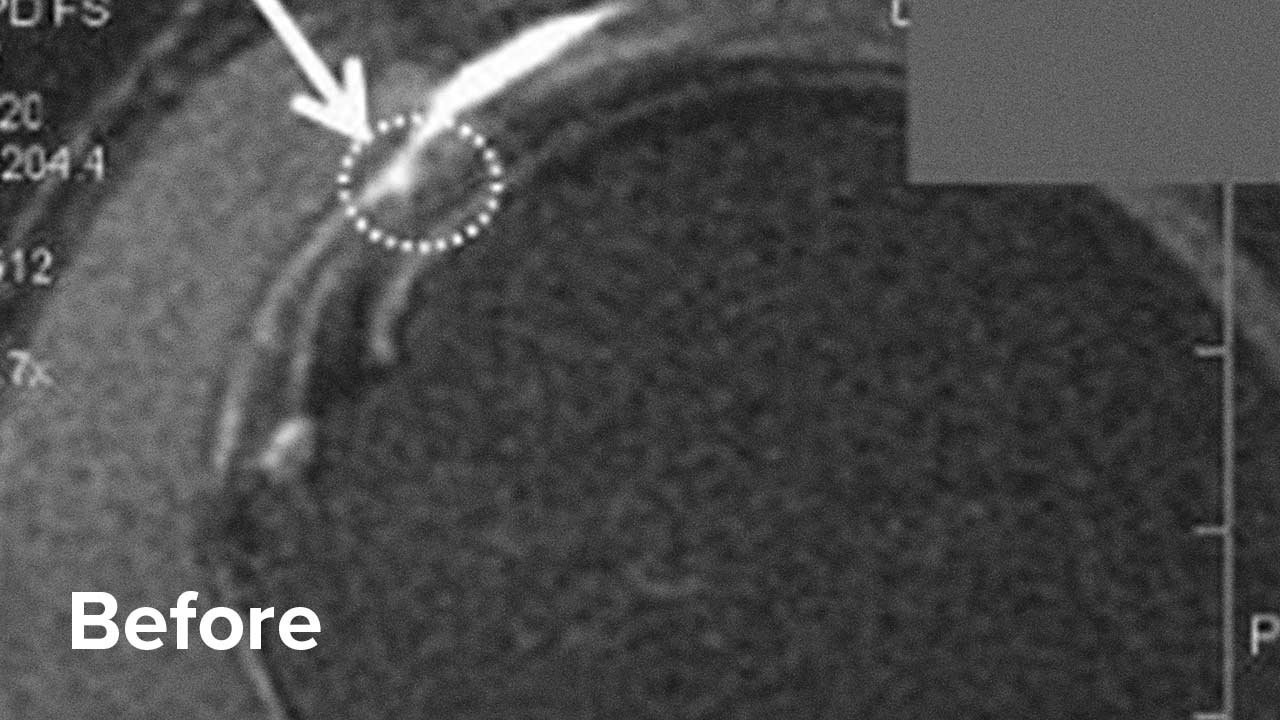

Take a look below at the outcomes of two of our patients who chose to have a Regenexx procedure for rotator cuff tear repair instead of surgery.

Scroll the arrow to the right to see the MRI of the rotator cuff before the treatment and to the left to see the outcome. The BEFORE shows a torn rotator cuff. The arrow points at a gap where the tendon should be. Once treated, the area will look like a dark band going diagonally, as seen on the AFTER.

Rotator cuff tear MRI – Patient 1